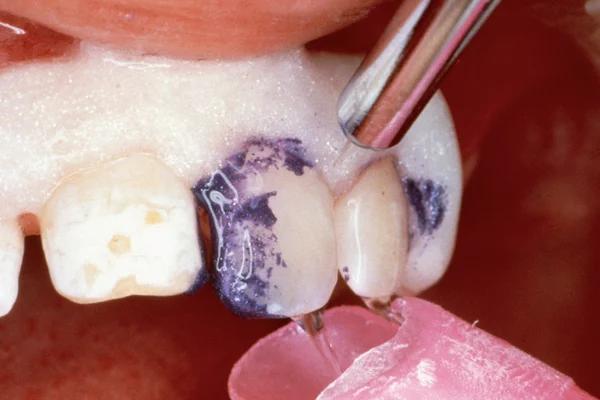

To improve isolation and soft tissue access, a retraction cord was placed before initiating the procedure (Fig. 2). The tooth was evaluated using a caries indicator dye (Kuraray Noritake Dental), helping to identify any remaining infected tissue beneath the dislodged composite (Fig. 3). Decay removal was completed with a diamond bur, and the enamel was bevelled using a starburst pattern to enhance aesthetic blending (Fig. 4). This preparation design was chosen for visual integration rather than bond strength enhancement.

Application of caries indicator dye to identify remaining infected tissue beneath the dislodged composite.